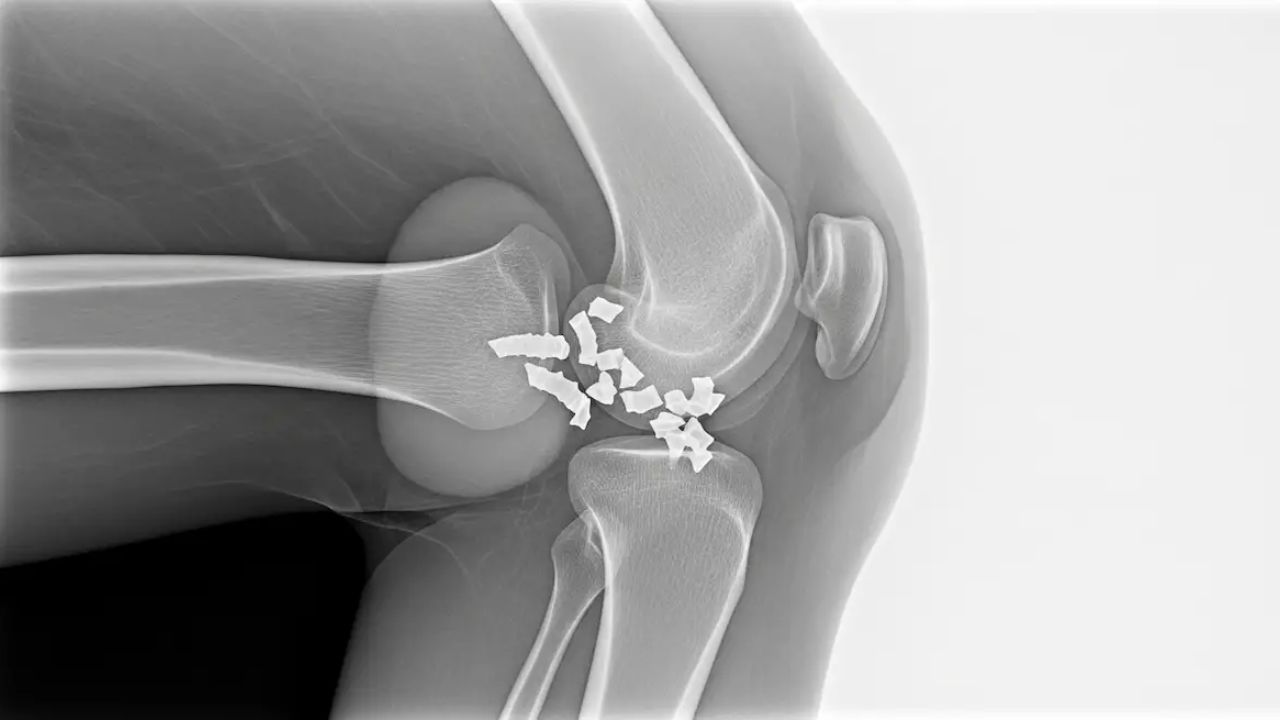

O diagnóstico é simples e realizado pelo ortopedista através do exame físico e da história clínica do paciente. O raio-x pode ser solicitado para descartar outras patologias, como fraturas ou tumores ósseos, e geralmente mostra a irregularidade ou fragmentação na tuberosidade da tíbia característica da síndrome. É importante tranquilizar os pais e o paciente de que se trata de uma condição autolimitada, ou seja, que tende a se resolver sozinha conforme o esqueleto amadurece.

O tratamento visa o controle da dor e a manutenção das atividades na medida do possível. Aplicação de gelo após os exercícios e uso de analgésicos são recomendados para as crises de dor. A fisioterapia é muito importante e foca no alongamento da cadeia posterior e do quadríceps para diminuir a tração sobre o tendão, além do fortalecimento muscular. Em casos de dor muito intensa, pode ser necessário reduzir temporariamente a carga de treinos, mas raramente é preciso parar o esporte totalmente. A cirurgia é extremamente rara e só considerada em adultos com sequelas dolorosas (ossículos soltos) que não melhoraram com o tempo.